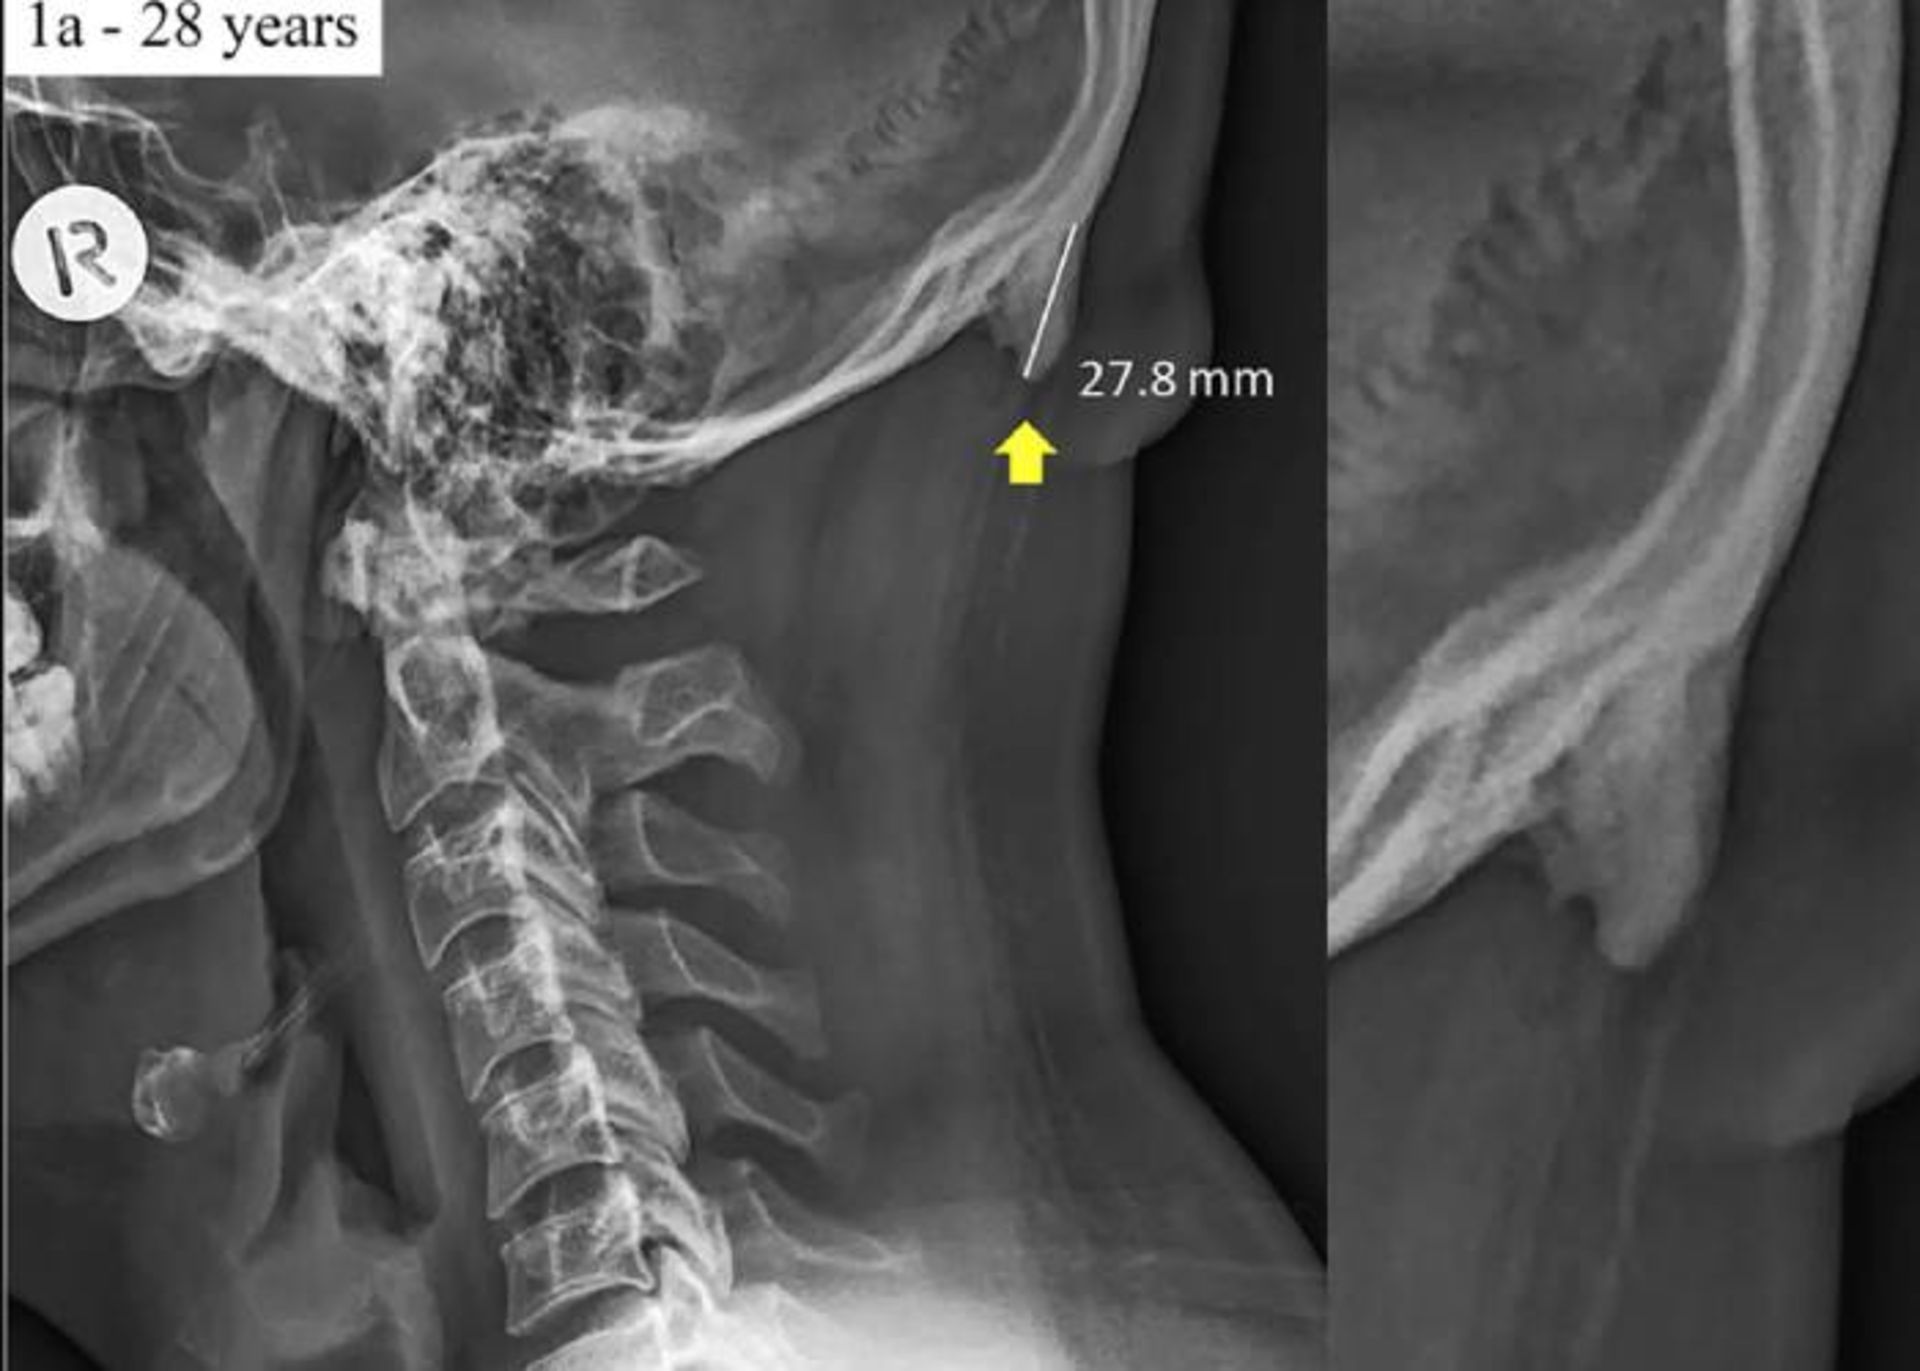

برجستگی پس سری

شکل 1a از مطالعه‌ی سال ۲۰۱۸ شاهار و سایرس که نشان‌دهنده‌ی یک برجستگی بیرونی پس‌سری بزرگ شده است